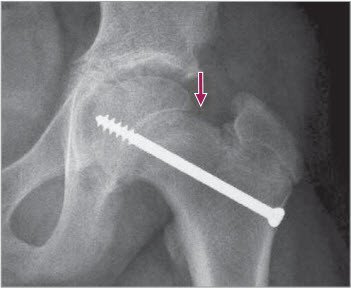

Abrutschen der Kalotte

1 Seitliche (Imhäuser) Aufnahme, links mit deutlichem Abrutschen der Kalotte nach hinten (Pfeil)